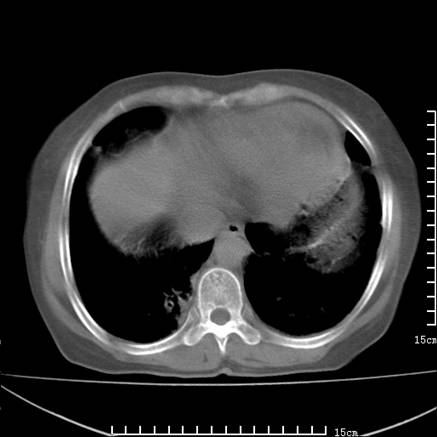

女,王某,58岁,咳嗽三个月余,基层医院二个月前诊为肺结核,用抗结核药二个月无明显疗效。

心包积液致肺瘀血.右侧周围型肺癌伴肺内转移,中间裂积液,叶间胸膜肥厚.右上肺大泡,右侧胸膜肥厚.

双肺继发型tb,心功能不全并肺淤血、心包、双侧叶间裂积液,肺大泡,右下胸膜肥厚钙化。